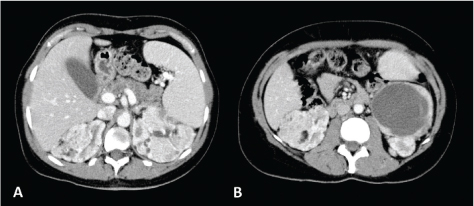

Fig 1

Figure 1. CT axial scan of the abdomen during venous phase of a 45-year-old woman with TS showing the presence of renal angiomyolipomatosis (A and B) and caliectasia at the level of the left upper calyceal group (A). Furthermore, a cystic lesion with solid peripheral tissue indissociable from the left inferior renal pole is evident (B). At the follow-up CT scan performed approximately 6 months later, the cystic lesion showed an increase of the solid component. Consequently, the patient underwent left nephrectomy and tumorectomy. Histological examination revealed the diagnosis of dedifferentiated liposarcoma.